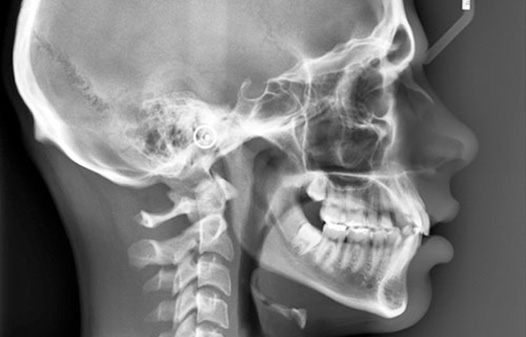

● Telerradiografía de cráneo perfil

● Radiología de cráneo con cefalostato frente y perfil

● Cefalometría